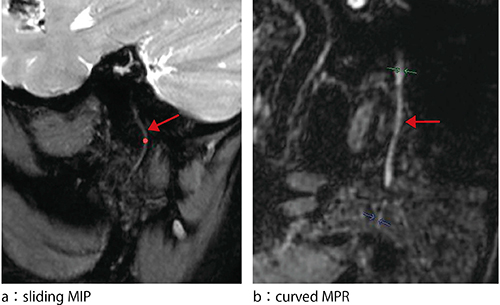

まずは,元画像のまま(図1 a),次にMPR(図1 b)で観察を行い,ほかにsliding MIP(図2 a),curved MPR(図2 b)などでの観察が考えられる。しかし,元画像のままでは,構造が細く画像の解釈が困難である。また,MPR,sliding MIPでは観察可能であるものの,断面をその都度ずらす必要があり,神経全体の観察には適していない。curved MPRでは,細部まで神経の走行を追跡できるものの,1本の神経しか描出できず,分岐していく神経には対応できない。このように,これまでの描出方法では分岐していく神経全体像をとらえることは困難であった。

図2 耳下腺内顔面神経の描出方法:sliding MIPとcurved MPR